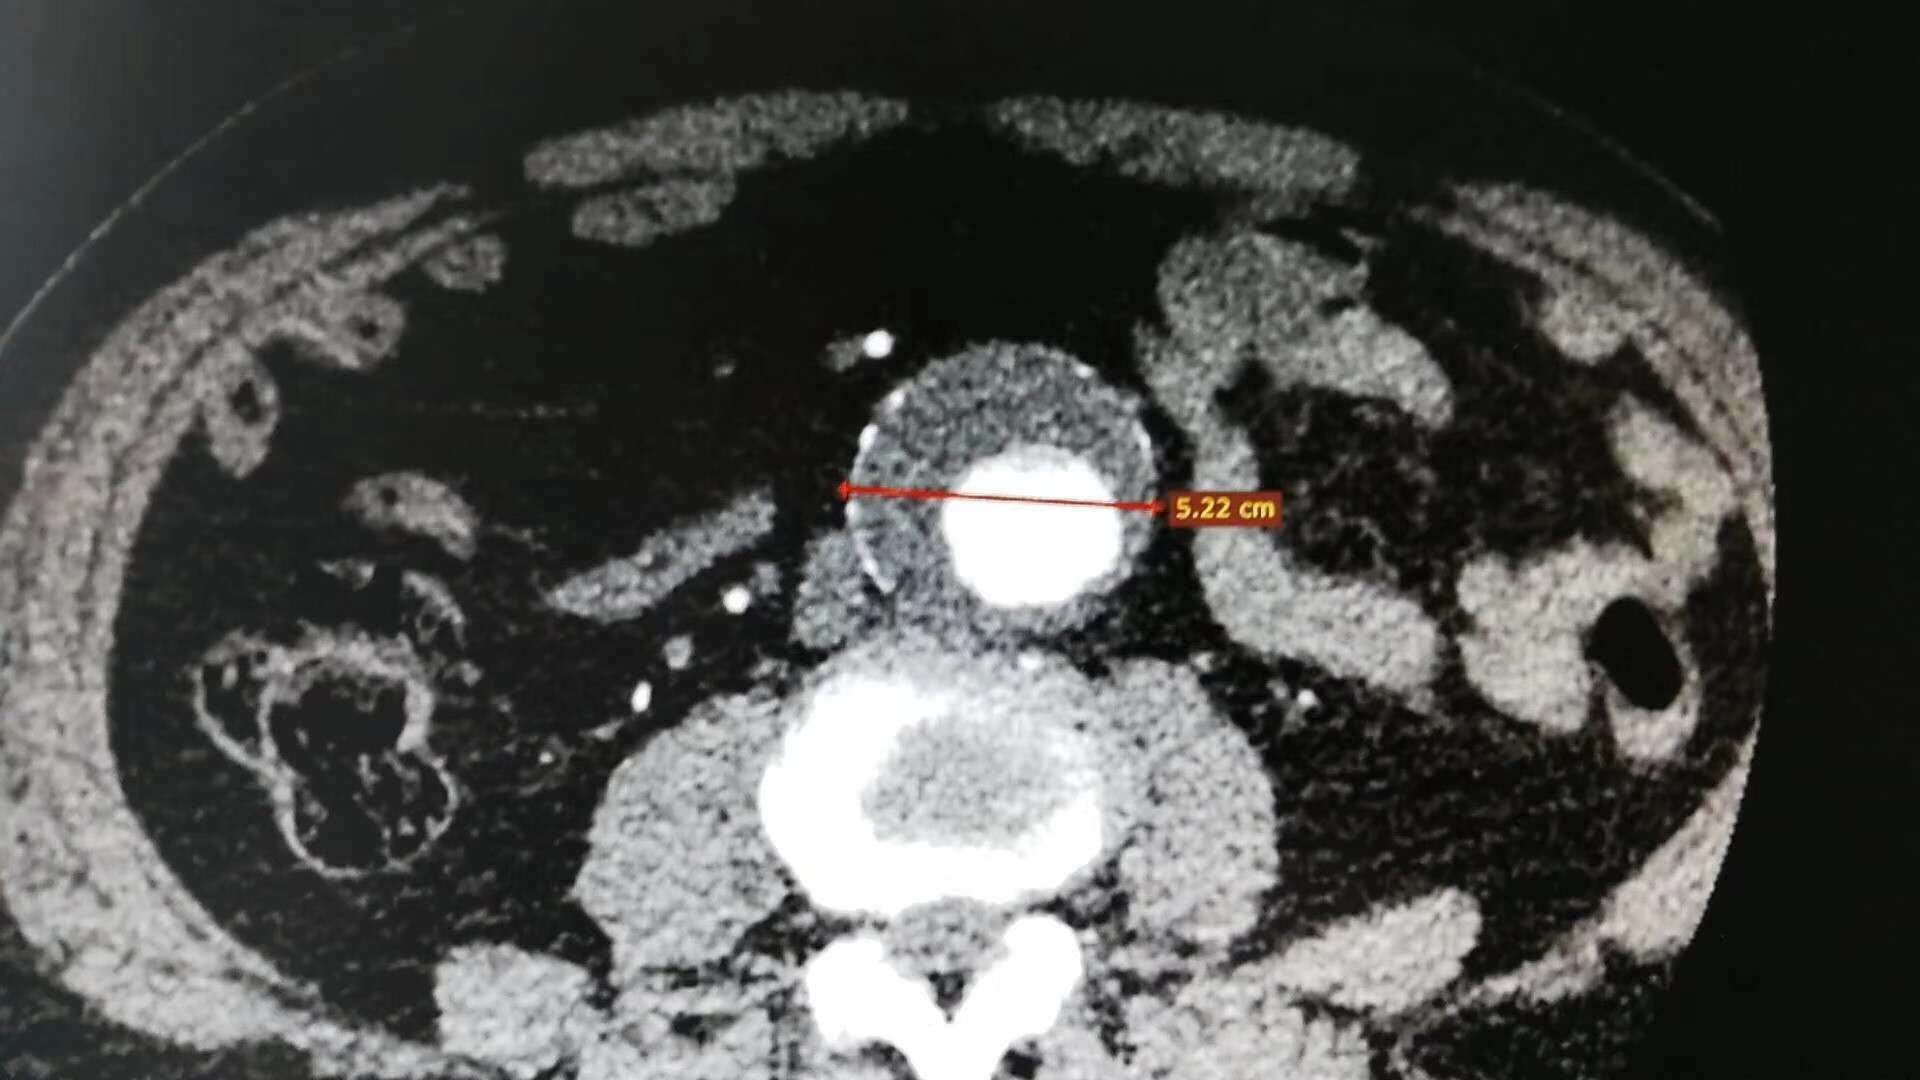

一例75岁男性患者3年前诊断腹主动脉瘤,3周前复查发现动脉瘤增大。近日我院成功为其行局部麻醉+强化麻醉下的全微创腹主动脉瘤修复术。只有两个长度0.5cm的手术切口,无需气管插管麻醉,手术时间一个小时,术后无需ICU过渡,恢复极快。除了造影时呼吸不易控制外几乎找不到缺点了。术后该患者恢复良好,已康复出院。